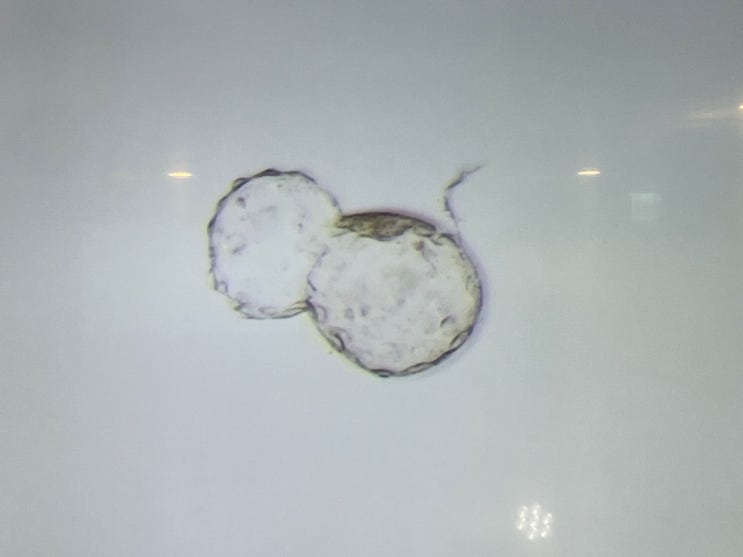

부천마리아 시험관 이야기 :: 어서와 희동(열매)아! (동결 5일배양 성공)

부천마리아 시험관이야기, 열매야 반가워:) 저-엉말 힘든 하루하루였다. 희아때 입덧이 심해서 둘째는 입덧...

둘째준비시작, 부천마리아 시험관 동결 5일배아 이식 이야기 (feat. 희동아 이리온)

부천마리아 시험관 동결 5일배아 준비 출산하고 10개월이 지났다. 고로 나의 육휴도 3-4달 남짓 남았다는 ...